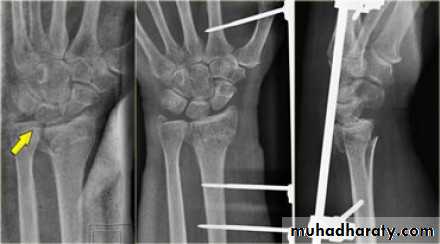

Upper limb

Fall on out stretched hand

xray

Management

Surgery